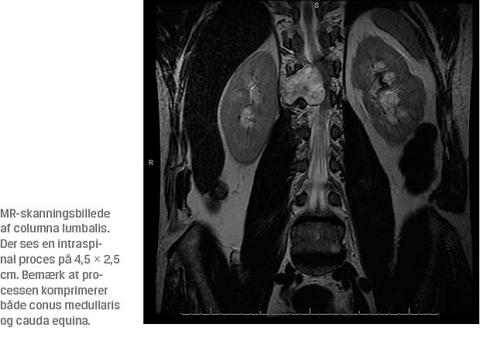

En efterfølgende MR-skanning af columna lumbalis viste et 4,5 × 2,5 cm stort timeglasneurinom, der var fremkommet i nerverod Th12 lokaliseret ekstraduralt ud for vertebrae Th12 og L1 og displacerede det intraspinale indhold mod venstre (durasækken, conus medullaris og cauda equina). Skanningen viste desuden spinalstenose på niveau Th12/L1. Der blev foretaget makrototal fjernelse af tumoren, og en patologisk undersøgelse viste schwannom, WHO-grad I. Et år postoperativt var smerterne og gangbesværet næsten forsvundet.